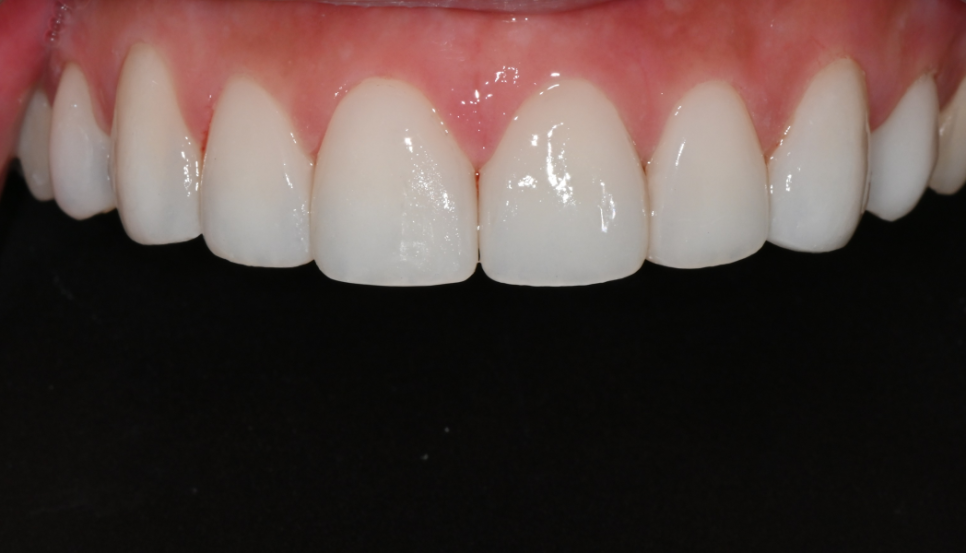

투명층 없이 깔끔한 잠실 라미네이트

최종 라미네이트는

환자분이 요청하신 대로

투명층을 거의 사용하지 않은 톤으로 제작됐습니다.

겉으로 볼 때 ‘라미네이트 느낌’이

강하게 드러나지 않도록

본래 치아 같은 매트한 광을 살렸고,

앞니부터 송곳니까지 이어지는 라인을

입술 움직임과 자연스럽게 맞춰 정리했습니다.

장착 후 거울을 보며

“인상이 깔끔하게 정리된 느낌이다”,

“밝은데 전혀 과하지 않다”

며 크게 만족하셨습니다.